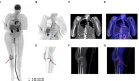

Posteriormente, tras la corrección de la deshidratación, se realizó tomografía computarizada abdominal que reveló hallazgos compatibles con pancreatitis crónica avanzada, incluyendo calcificaciones parenquimatosas, dilatación irregular del conducto pancreático principal y pérdida de la arquitectura glandular normal.

Además, se identificó trombosis aguda de la vena esplénica con hematoma esplénico asociado. No se observaron lesiones ocupantes de espacio ni signos de abscesos pancreáticos.